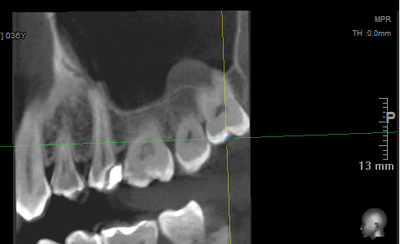

Ну, компьютерную томографию (3D объемный снимок) можно сделать - где угодно.

А для того, что ортопантомография (ОПТГ, обзорный или панорамный снимок зубов), является плоскостным, а значит происходит наложение каждой детали снимка послойно друг на друга. Следовательно, рассмотреть объект исследования, в частности, область зуба мудрости, расположенного рядом нижнечелюстного нерва, во всех плоскостях, под иным углом или другой проекции невозможно. КЛКТ (Конусно-лучевая компьютерная томография), напротив дает нам такую возможность.